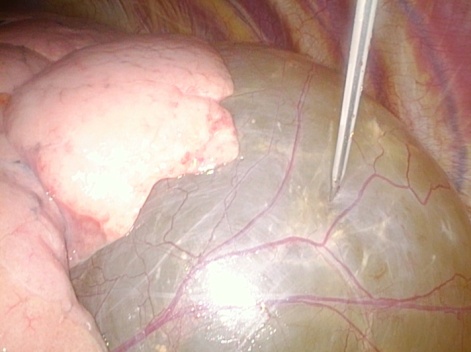

The patient underwent emergency surgery performed by general surgeons, involving adhesiolysis and debridement of the strangulated intestinal loops, and was subsequently referred to us for observation. Spirometry showed normal respiratory function, and echocardiography ruled out compression on the heart and pericardial effusion. Due to considerable size of the cyst the patient underwent two-port VATS, under general anesthesia using a 35 French left-sided double-lumen endotracheal tube. Surgical access was obtained via a 2 cm skin incision through the fifth intercostal space (5 th ICS) on the anterior axillary line, and at 7 th ICS on the mid-axillary line. A giant, spheroidal mediastinal neoformation with a vascularized surface is detected (Figure. 3).

Figure 3. VATS reveals a giant, spheroidal mediastinal neoformation with a vascularized surface

An intra-operative needle aspiration is performed to reduce the size and facilitate its removal (Figure. 4).

Figure 4. An intra-operative needle aspiration is performed